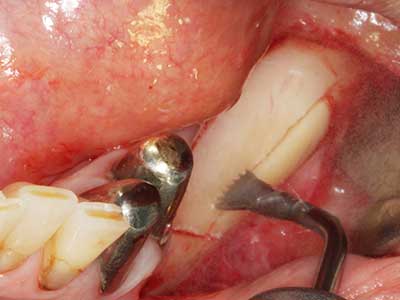

Indication: Preparations close to nerve tissue

As noted above, indications for piezo surgery can also be found in the field of conservative dental surgery. Special working tips simplify the exposure of root tips and make it easier to protect nerves and sinus mucous membranes, particularly in the lower premolar and upper posterior tooth regions. Angled diamond tips are used to precisely prepare the resection cavity for the retrograde root filler material for unsealed apical obturation. The ultrasonic technology means the tips can be very slender, which improves the view and the size of the access cavity. As a result, the application of ultrasonic surgery for this indication is one of the standard procedures for apical resection (Del Fabbro, Tsesis et al. 2010, Scarano, Artese et al. 2012).

Indication: Apical resection

When surgical procedures are performed on bone in the immediate vicinity of sensitive structures such as blood vessels or nerves, rotary instruments pose a significant risk of iatrogenic injury. Piezoelectric devices can be helpful for preparation of bone covers and removal of hard tissue close to nerves, particularly for exposure of nerves after iatrogenic injury but also during nerve lateralization for resective and reconstructive procedures or implant placement (Fig. 17-20). Light contact between the piezotip and the nerve does not generally result in damage but proceeding incautiously with saw-like motions or attachments where a residual bone substrate remains may cause temporary or even permanent nerve damage. However, the risk of damage is considered to be substantially lower than when using saws or milling instruments (Pereira, Gealh et al. 2014).